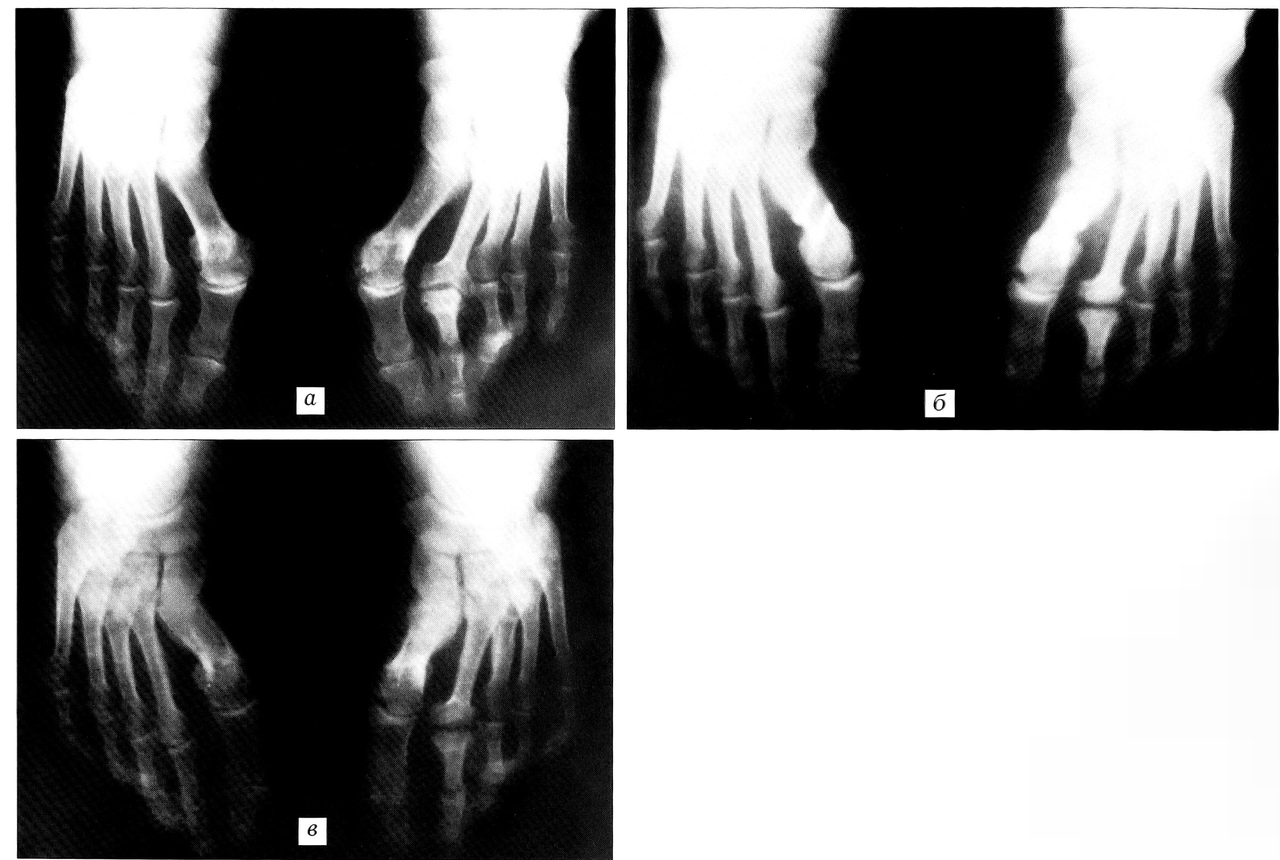

Рис. 4. Рентгенограммы той же больной Ф. до операции (а), через 6 мес (б) и 8 мес (в) после операции (металлоконструкции удалены).